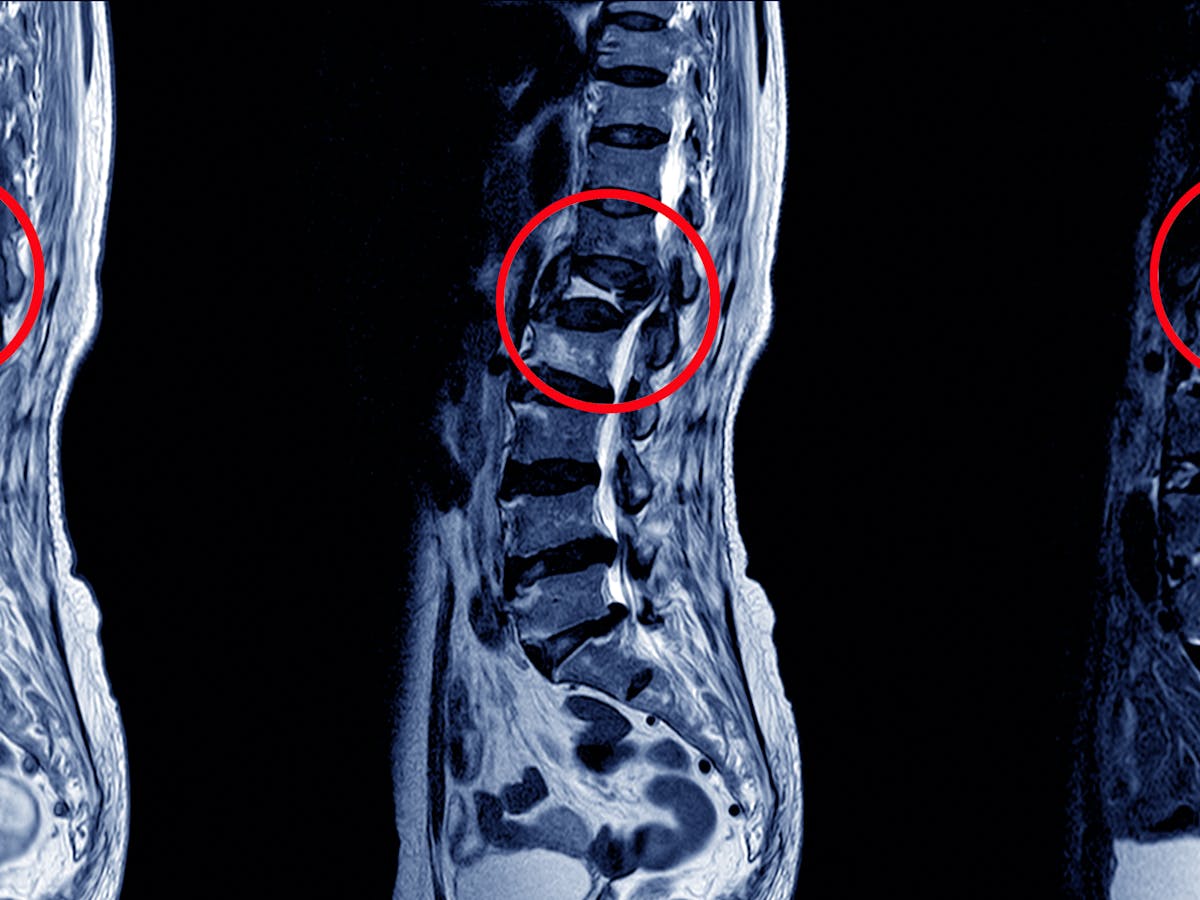

The disease can affect any bone or the joint but most common bones affected are spinal vertebra knee hip shoulder and elbow bones and joints. Certain factors such as poverty overcrowding old age malnourishment drug abuse diabetes mellitus hiv infection can predispose tuberculosis of bone. The usual site of tb is the lungs pulmonary tb but other organs can be involved.

This means that the bacteria can be spread to other people. Tuberculosis generally affects the lungs but can also affect other parts of the body. Tuberculosis of the bone is associated with pulmonary tuberculosis.

For example tuberculosis of the spine may give you back pain and tuberculosis in your kidneys might cause blood in your urine. From there they can move through the blood to other parts of the body such as the kidney spine and brain. Most infections show no symptoms in which case it is known as latent tuberculosis.